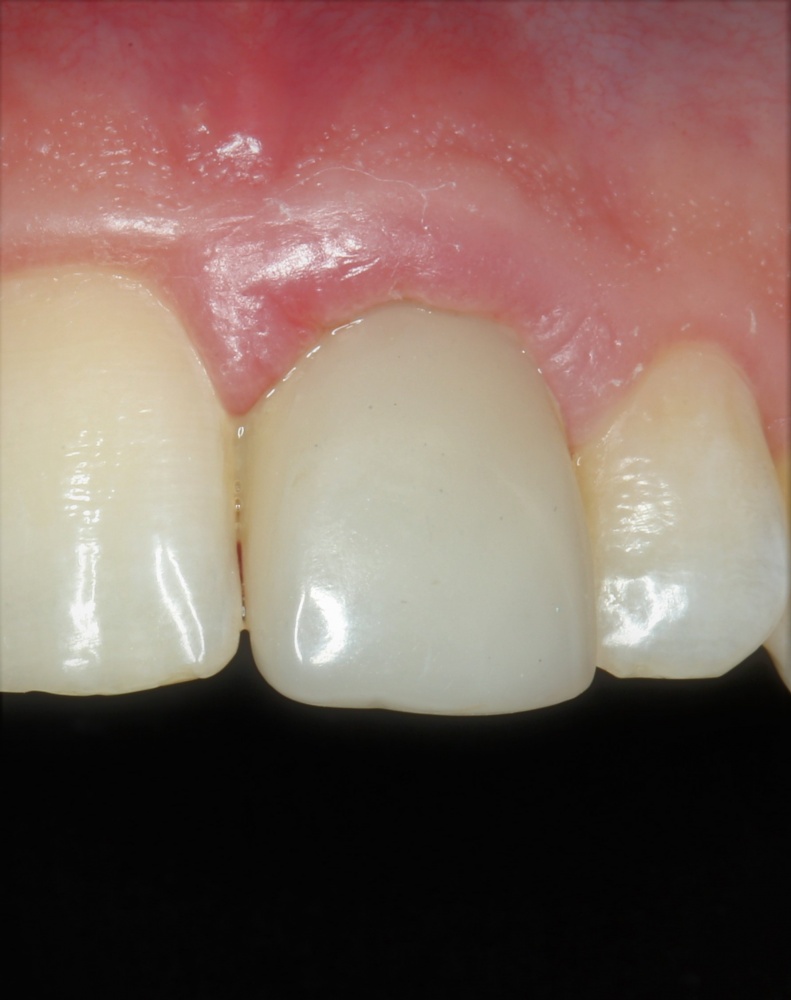

К счастью, уже через 6 недель после операции вдруг выяснилось, что ничего исправлять не нужно:

Фактически, нам осталось лишь дождаться приемлемого уровня остеоинтеграции имплантатов,  — примерно 2-3 месяца, — и можно переходить к постоянному протезированию.

Постоянные протетические конструкции

Через три месяца мы сняли коронки с имплантатов, чтобы оценить качество формирования десневого контура:

С этого момента можно перестать переживать — десневой контур сформировался правильно, мы получили достаточный объём и качество окружающей платформу имплантата десны. Можно приступать к изготовлению постоянной протетики. Подрядчиком стала зуботехническая лаборатория French Creative, одна из топовых лабораторий Москвы.

И вот, в жизни Марии наступил долгожданный день — окончательная фиксация керамических коронок на установленные имплантаты:

При этом, она ни дня не оставалась без зубов, была полностью социализирована и жила обычной жизнью. Спустя 5 месяцев после удаления, поставленную Марией клиническую задачу можно считать решёной. Но это с её точки зрения. С нашей же, всё самое интересное только начинается.